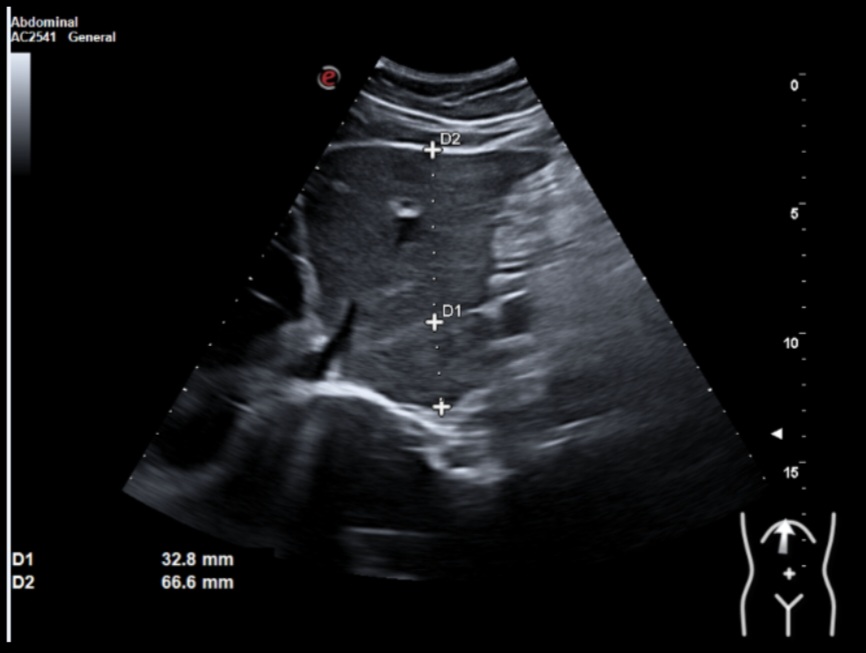

Ecografía clínica: múltiples lesiones en parénquima hepático bien delimitadas de hasta 2 cm, hipoecogénicas, en ambos lóbulos. Tamaño normal del hígado (15 cm) pero bordes obtusos. Vía biliar no dilatada. Vesícula alitiásica. Porta de calibre normal. Área pancreática no visualizada por gas intestinal. Ambos riñones normales. Vejiga vacía, no valorable.

Dados los hallazgos se solicitó ecografía reglada que informaba de múltiples lesiones hepáticas sospechosas y afectación adenopática infradiafragmática. Se recomendó completar estudio mediante TAC estadiaje.